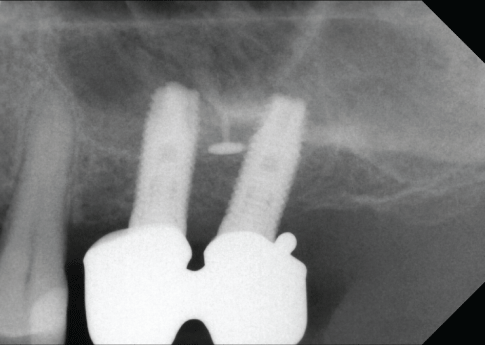

图1:异体骨块移植术后和开放刮牙术中的手术部位24和25。

使用成骨螺钉(usstomp)将骨块固定到位,使用颗粒状异体替代材料(Puros Allograft Spongiosa Partikel[松质骨颗粒],Zimmer Dental GmbH, Munich)将小块不均匀的斑块平整(图1)。